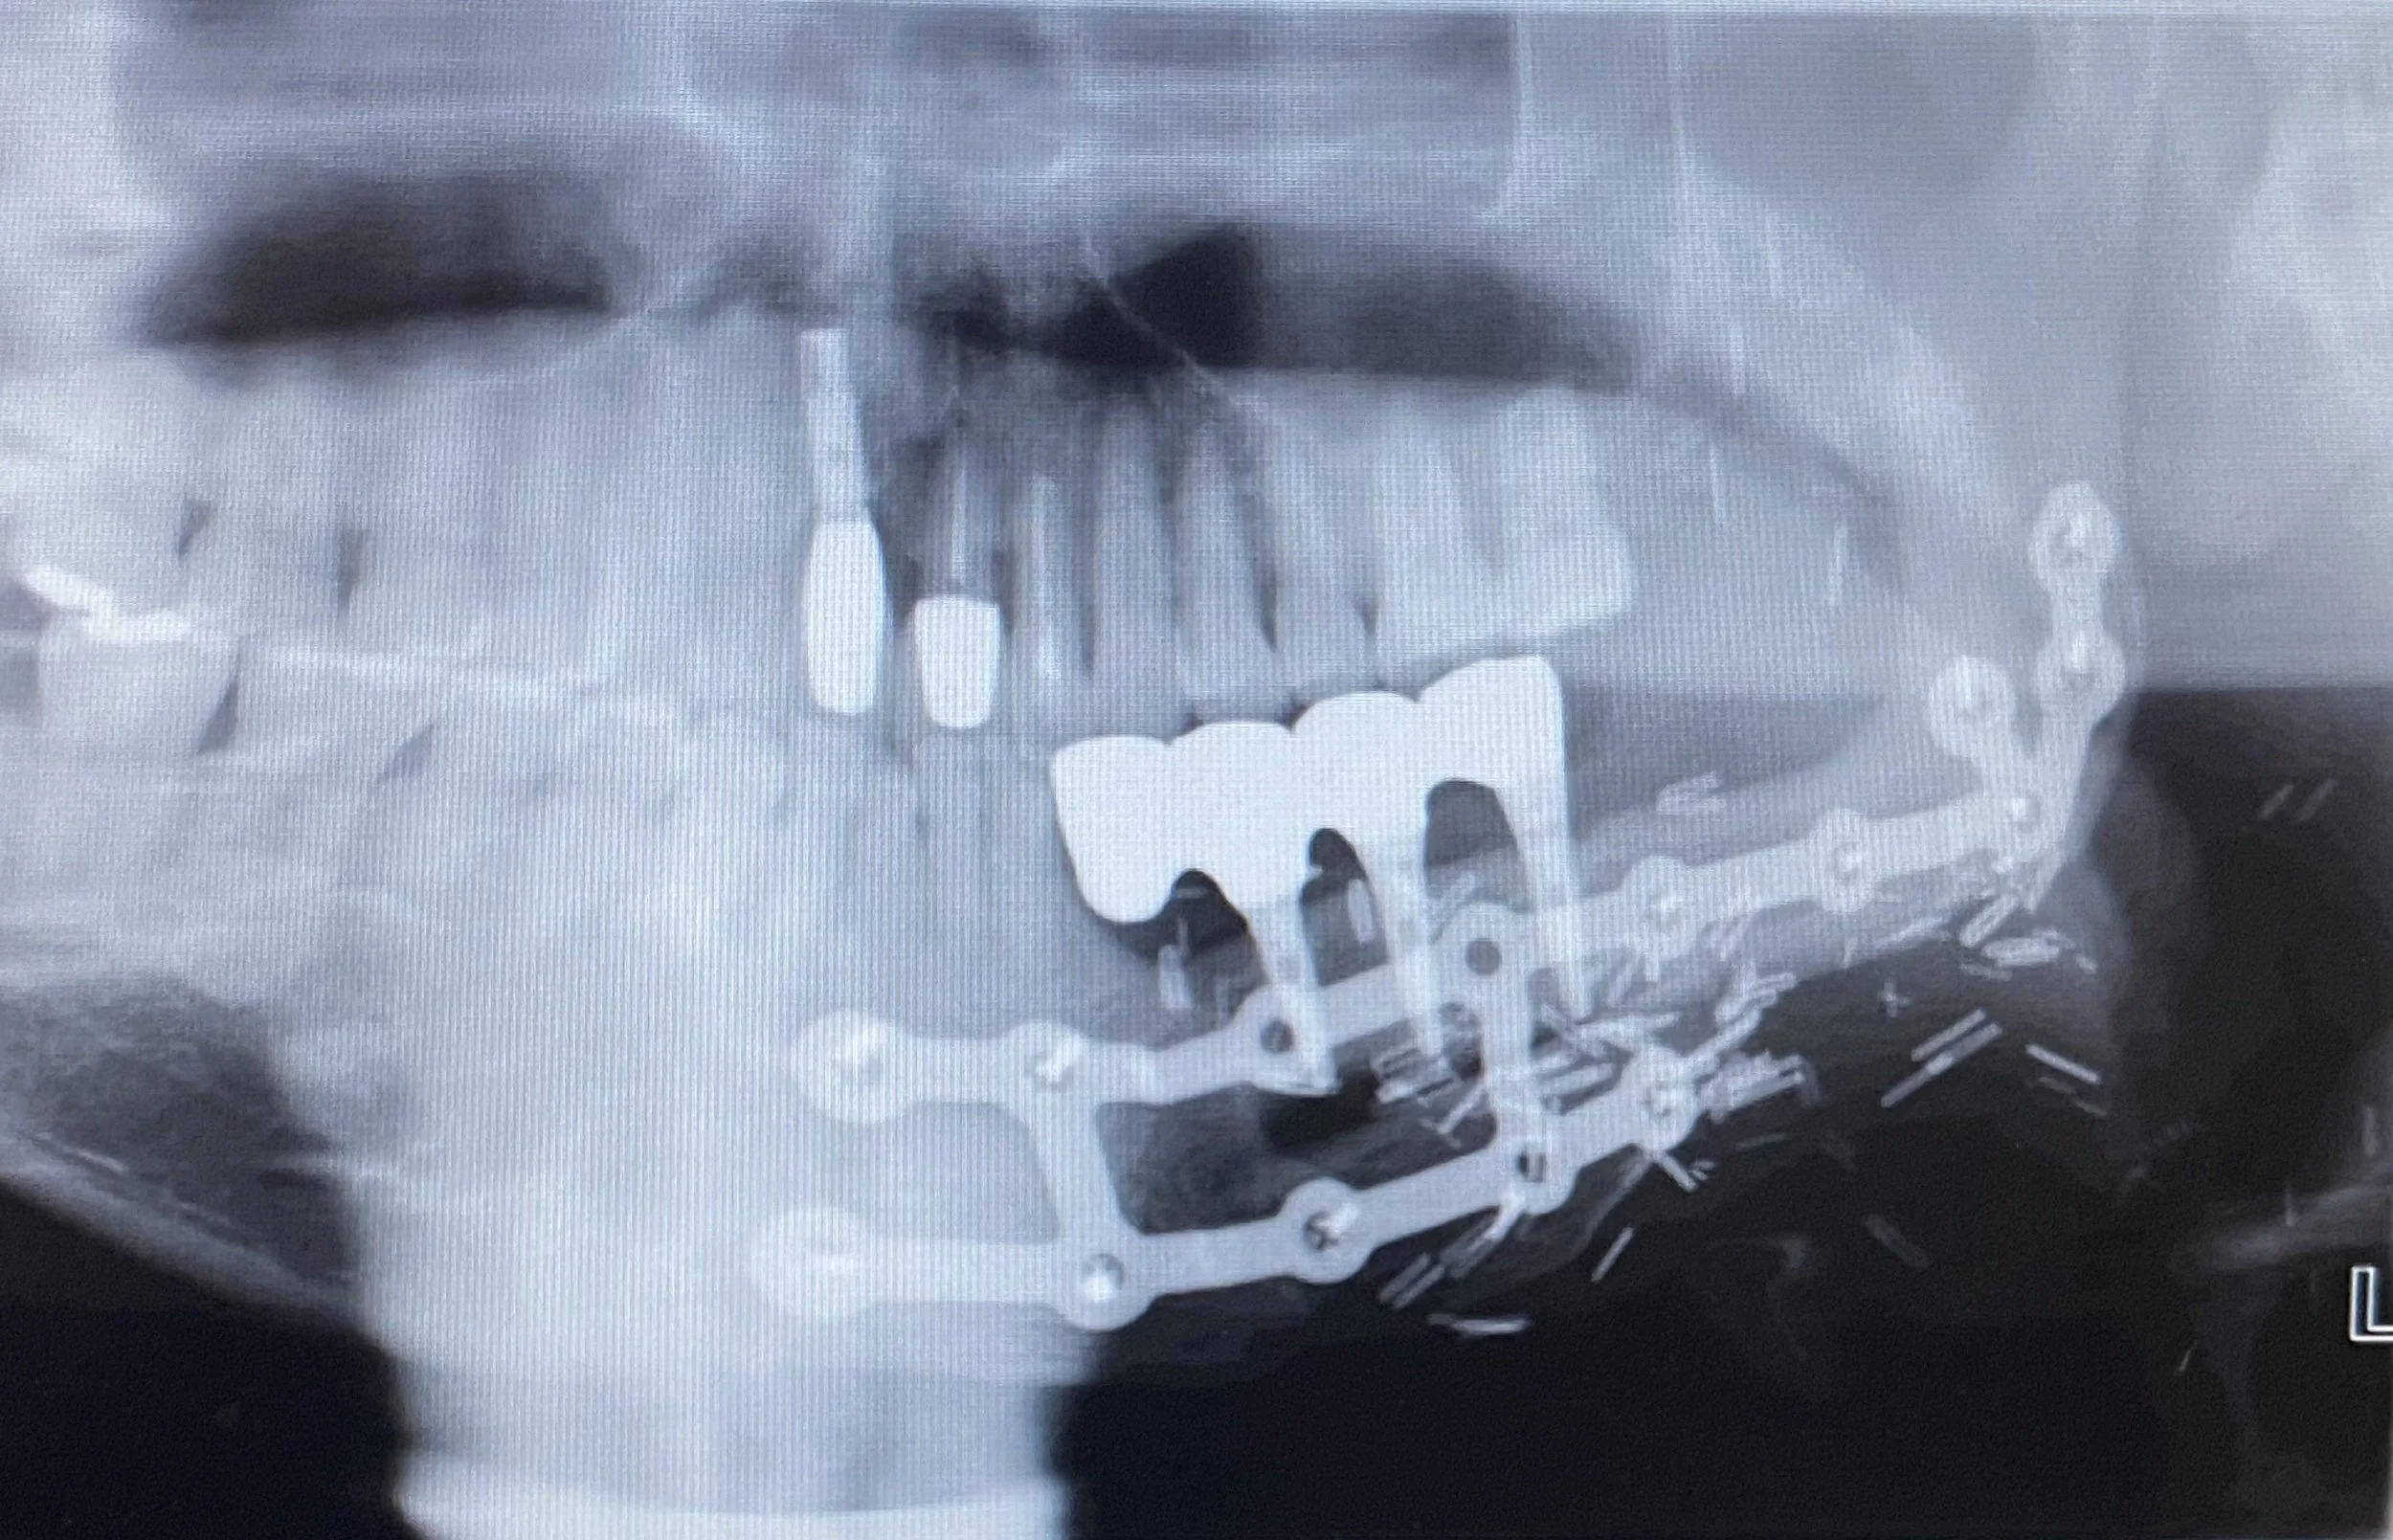

This 50 year old patient unfortunately developed cancer in his mouth on the lower left hand side which required complete resection or removal of the teeth, gums and lower left jawbone by a Facio-Maxillary Surgeon.

-

The lower jawbone was reconstructed by harvesting bone from the tibia of the leg along with a soft tissue graft consisting of calf muscle and surrounding fat tissue. Two pieces of bone were splinted in place with metal plates and screws to the remaining jawbone .

The patient was referred to me at Lismore in 2021 to replace the missing teeth with a fixed prosthesis involving an implant bridge. I designed the bridge on an OPG radiograph and issued instructions to my ceramist technician to fabricate a diagnostic wax up of the future teeth .

This OPG radiograph illustrates the completed 3 implant fixture and note that two of the metal splints had to be removed for implant placement. Note there was insufficient bone in the lower left canine region to place an implant which necessitated the designing of a cantilevered bridge tooth